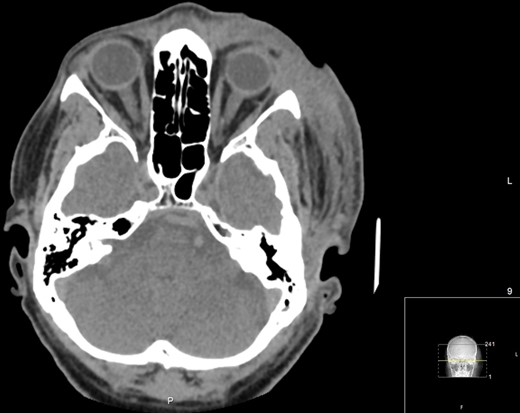

The patient’s condition began to stabilize 24 hours after the surgical intervention. A repeat CT orbit revealed persistent, though reduced, soft tissue swelling with no orbital breach or collections (Fig. 4). The patient improved and was discharged from hospital 19 days after admission. At 3 months, the wounds had healed and there was no visual deficit (Fig. 5). He is awaiting reconstructive surgery under the maxillofacial and the oculoplastic teams.

Axial CT Orbits performed on Day 7 post-debridement, showing improved left periorbital soft tissue swelling. No post-septal involvement, orbit breach or identifiable collections.